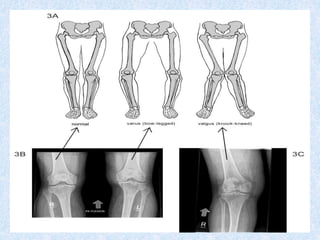

1-valgus deformity (bent outward), varus deformity

(bent inward) appear with joint instability.

Deformity of knee:-

1-valgus deformity (bentoutward), varus deformity (bent inward) appear with joint instability. 2-synovial effusion (demonstrated with patellar tap). 3- Baker cyst:- extension of inflamed synovium into popliteal space, causing pain and swelling. high pressure generated by flexion of knee can cause rupture of cyst into calf, manifested as calf swelling, tenderness and pitting edema. Deformity of knee:-